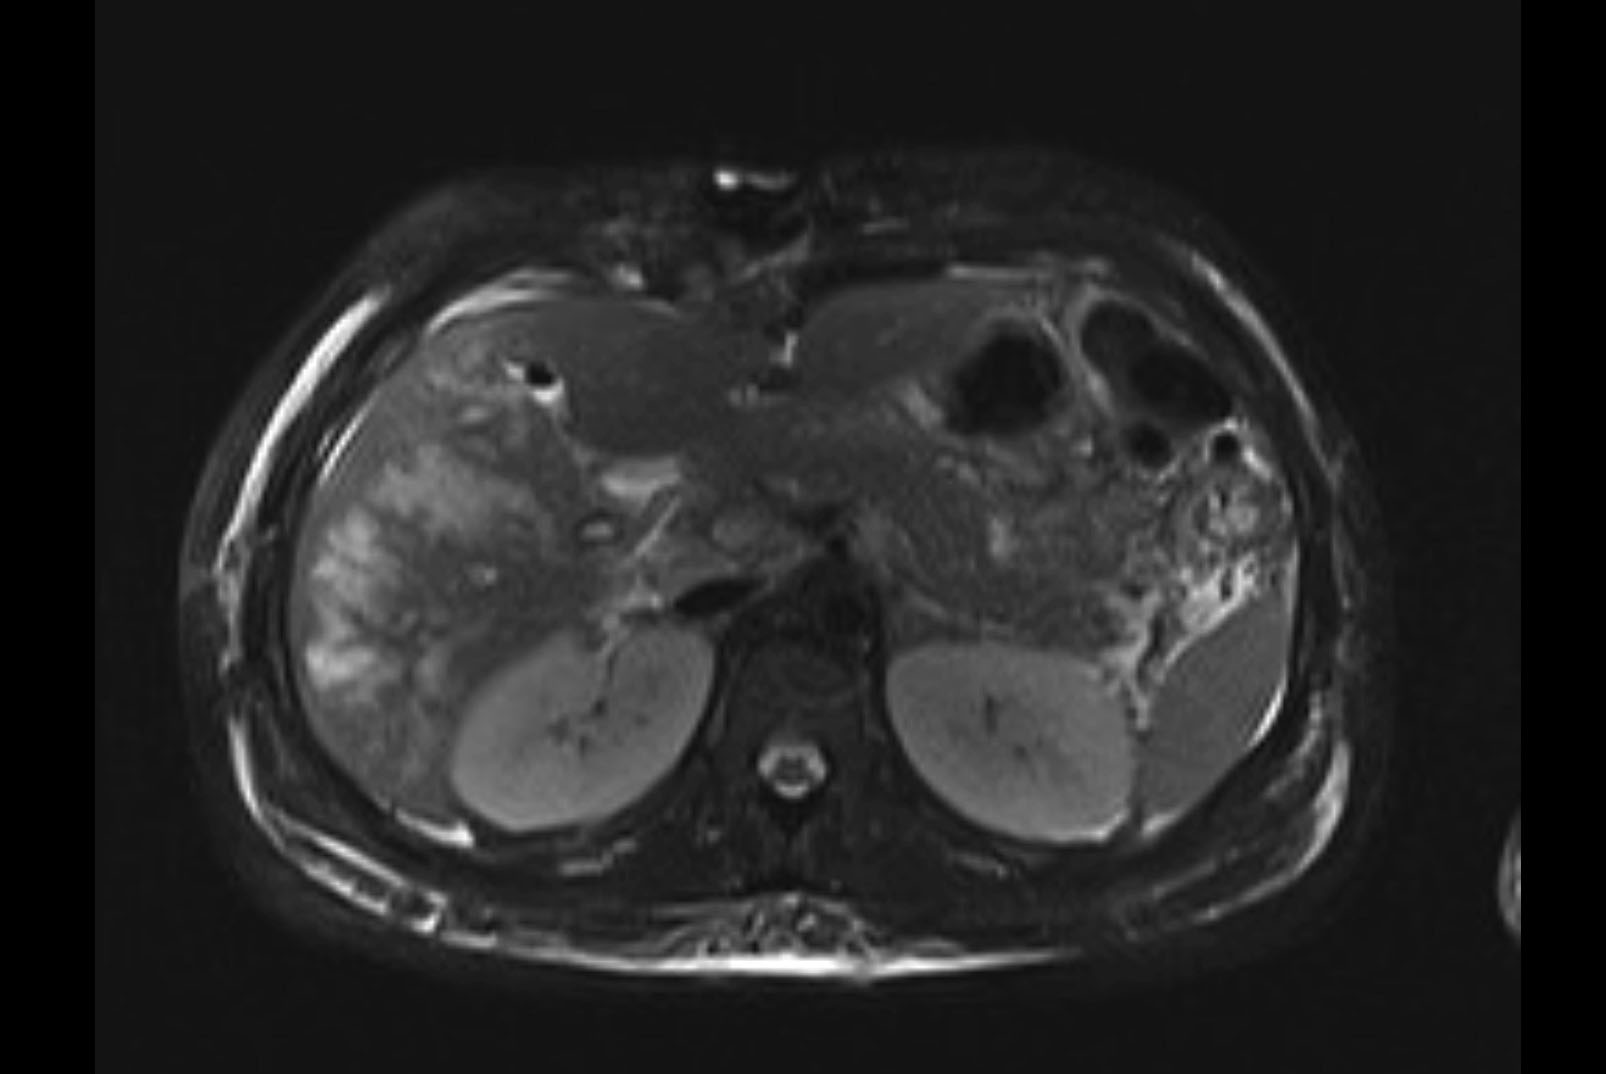

Imaging Analysis

Look through the patient's CT scan to identify any areas of concern for the necessary procedure.

MRI T1

MRI T2

Based on initial findings, which issue(s) would you be most concerned about?